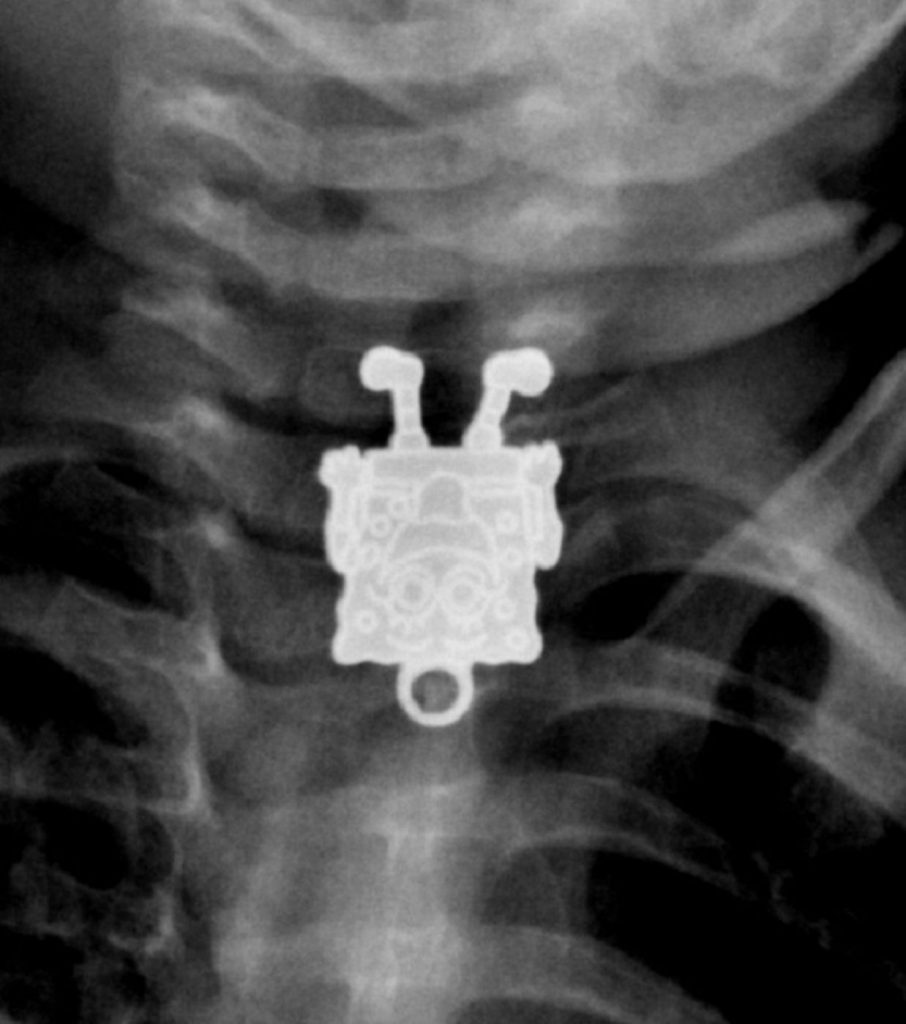

Sünger Bob

Kontrole gelen 16 aylık bir bebeği kontrol eden doktorlar, röntgende Sünger Bob Kare Pantolon’u görünce çok şaşırmışlar. Sonradan anlaşıldığına göre bebek, kız kardeşinin Sünger Bob şeklindeki kolye ucunu yutmuş. Doktorlar, nesneyi hiçbir sorunla karşılaşmadan çıkartmayı başarmışlar.